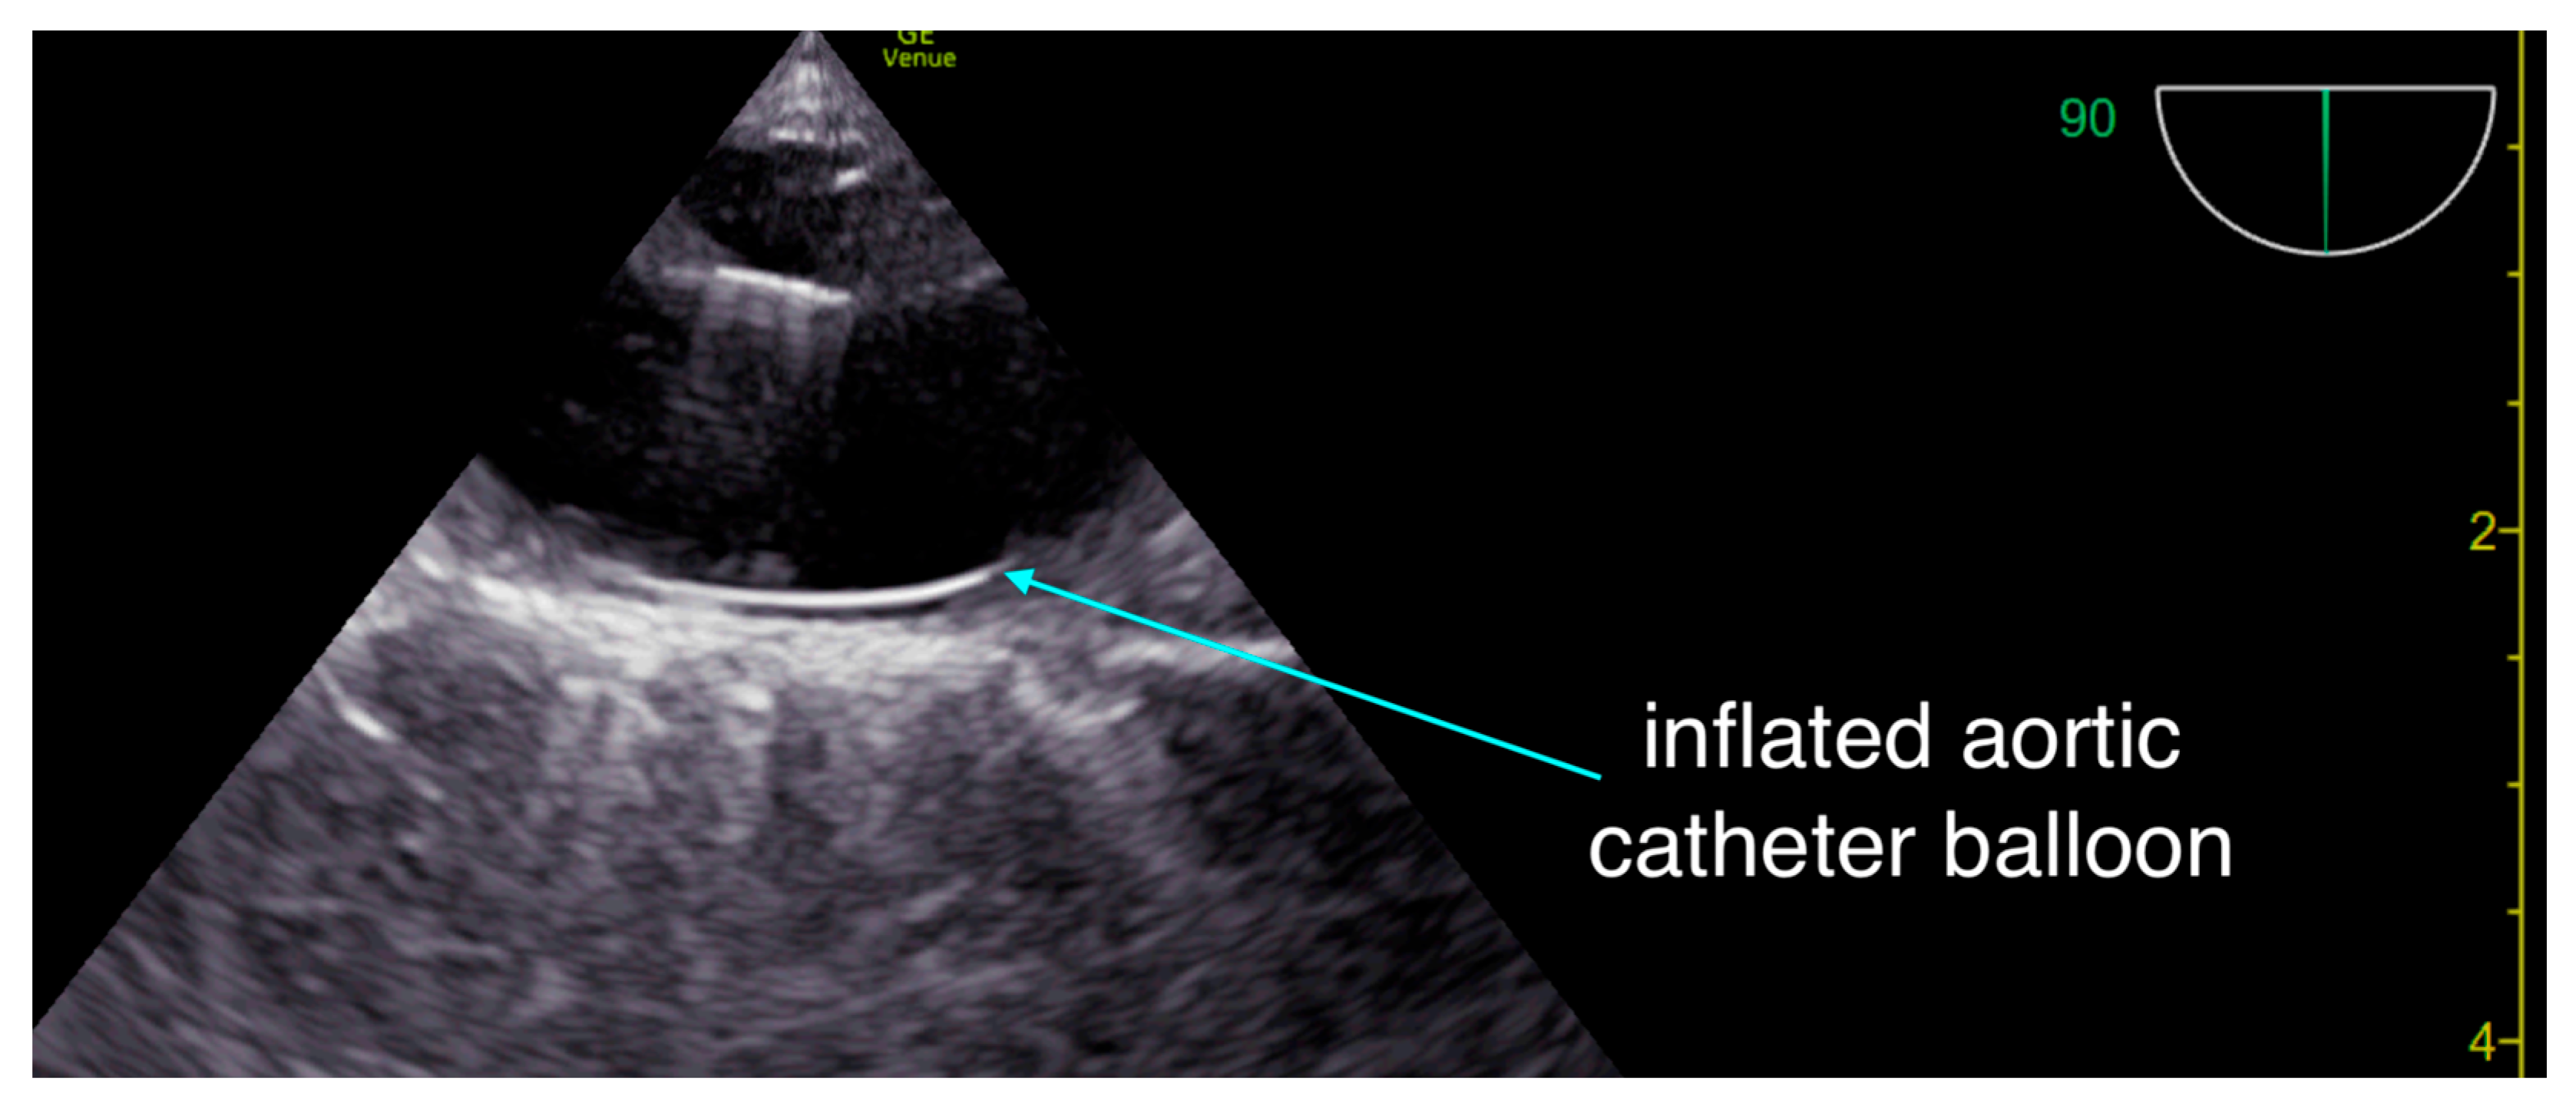

At 30 minutes, despite thrombolysis, ROSC had not been achieved. Given ongoing electrical activity and adequate chest compressions, a resuscitative aortic occlusion catheter (COBRA-OS, FrontLine Medical Technologies, London, ON, Canada) was inserted via the femoral artery under ultrasound guidance and inflated after approximately 40 minutes of CPR.

Figure 2. Our team uses resuscitative trans-esophageal thoracic ultrasound to ascertain appropriate guidewire placement in the thoracic aorta and to monitor appropriate balloon inflation and position - in addition to monitoring for appropriate position of chest compressions.

Resuscitative transesophageal echocardiography (TEE) was pivotal throughout the arrest, first confirming appropriate compression vector and absence of LVOT obstruction, and later tracking evolving ventricular function. In addition to its diagnostic role, TEE can serve as a continuous hemodynamic monitor, even during transport [3,4]. Unlike transthoracic views, which are often impossible due to chest compression devices and immobilization, the indwelling probe allows uninterrupted visualization of ventricular filling and contraction. In this case, TEE enabled optimization of chest-compression quality, verification of guidewire placement for the aortic occlusion catheter, and continuous reassessment of perfusion state—functions that extend its utility far beyond diagnosis.

Resuscitative aortic occlusion - the physiologic rationale in non-traumatic cardiac arrest lies in selectively augmenting coronary and cerebral perfusion while minimizing systemic catecholamine burden [5]. By creating a proximal pressure gradient favoring central organ perfusion, aortic occlusion can enhance myocardial and cerebral flow without the deleterious microcirculatory constriction caused by high-dose vasopressors. In this case, the improvement in cardiac motion after balloon inflation suggests that mechanical augmentation of perfusion pressure may have contributed to achieving ROSC, though the contribution of delayed thrombolysis cannot be excluded.